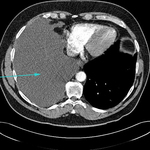

CT scan showing loculated pleural effusion

From the collection of Dr Ami Rubinowitz; used with permission